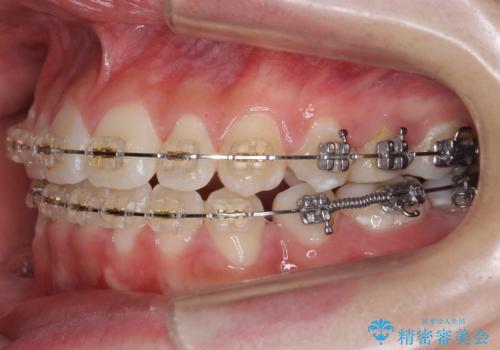

- 矯正装置

- 審美装置

下の小臼歯を抜歯しましたが、その代わり下の親知らずを残して咬ませたので、歯の数は変わっていません。

ただし、左下の親知らずを残すには厚みのある歯ぐきを処置しています。(ディスタルウェッジ)

左上奥歯は、矯正後セラミックインレー修復を行なっています。

今回は左下の小臼歯を1本抜歯してるのと、手術を行なって親知らずを顎に収めることができました。